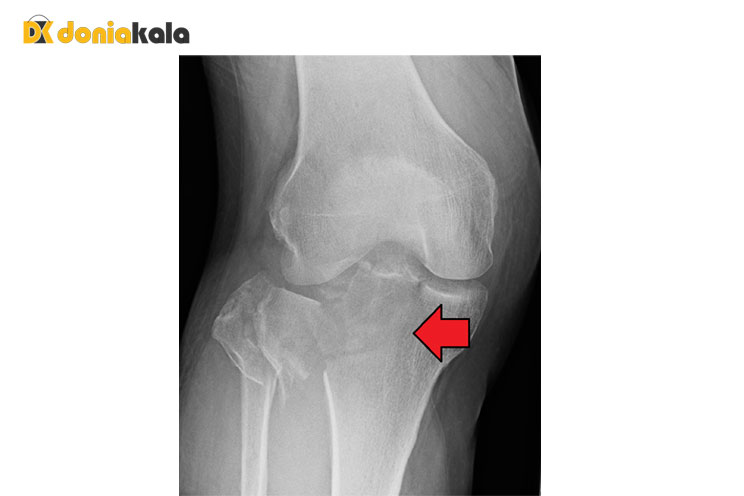

چشم انداز: شکستگی استخوان درشت نی یا ساق پا شایع است و می تواند در بسیاری از شرایط ایجاد شود. آنها می توانند در هر نقطه از استخوان رخ دهند و انواع شکستگی را شامل می شوند. شکستگیها میتوانند جزئی باشند و زمان کوتاهی برای بهبودی یا جدیتر داشته باشند و نیاز به جراحی و زمانهای بهبودی گستردهای داشته باشند. دورنمای بلندمدت شکستگی درشت نی معمولا خوب است اما به شدت آسیب و سایر عوامل مرتبط با سلامتی بستگی دارد. پزشکان میتوانند در طول فرآیند ارزیابی و بهبودی، چشماندازی طولانیمدت برای فرد فراهم کنند، زیرا پای او بهبود مییابد.